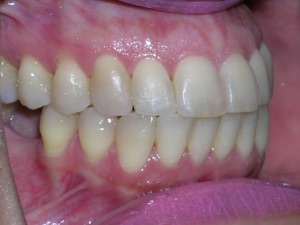

Here are the results.

Hope you like it too!